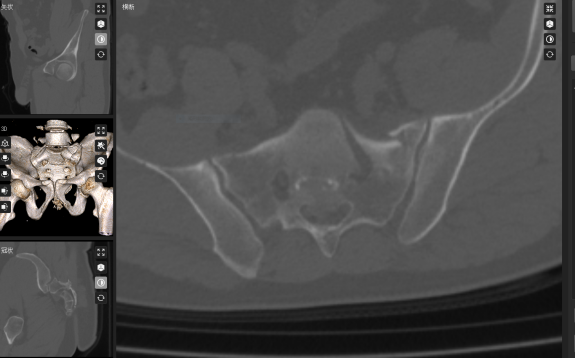

急诊CT显示: 腰椎多处横突骨折、骶骨“爆裂”性骨折、肾脏损伤、失血性休克!更危急的是,碎裂的碎骨块死死卡压神经通道,骶神经受压,患肢疼痛难忍。

术前:骶骨骨折,骶神经受压。

术前,叶军博士将患者的骨盆骶骨CT数据导入骨科机器人数字平台,进行三维重建和精准分析。通过数字化技术,医生能够清晰看到骶骨骨折移位及骶前孔受压的具体情况:骶骨体骨折塌陷,左侧骶骨翼受侧方挤压,骶1骶前孔前方受碎骨块压迫。